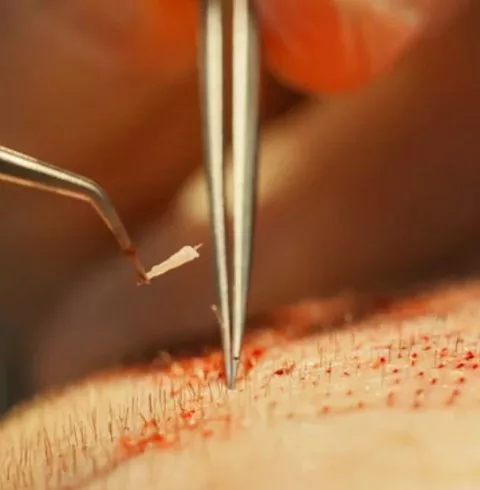

يعتمد طبيب الأسنان في هذه العملية على قطع معدنية صغيرة وإسطوانية الشكل تشبه مسامير البرغي يتم زراعتها في مكان السن المفقود وتثبيتها في عظام الفك ، ليتم استخدامها كجذور ثابتة للأسنان المزروعة . بعد ذلك يتم إتاحة فترة تتراوح ما بين 2 إلى 6 أشهر ليتم خلالها التعافي بشكل كامل ولضمان التحام القطع المعدنية مع عظام الفك.

بعد اكتمال فترة التعافي يتم تحديد موعد جديد مع طبيب الأسنان لتركيب الأسنان الصناعية المناسبة وتثبيتها بشكل جيد على الجذور المعدنية المصنوعة من التيتانيوم ، لتعمل هذه الجذور على تدعيم الأسنان الجديدة وتثبيتها لأطول فترة ممكنة ، والتي قد تستمر مدى الحياة في حالة العناية بها وبنظافتها.